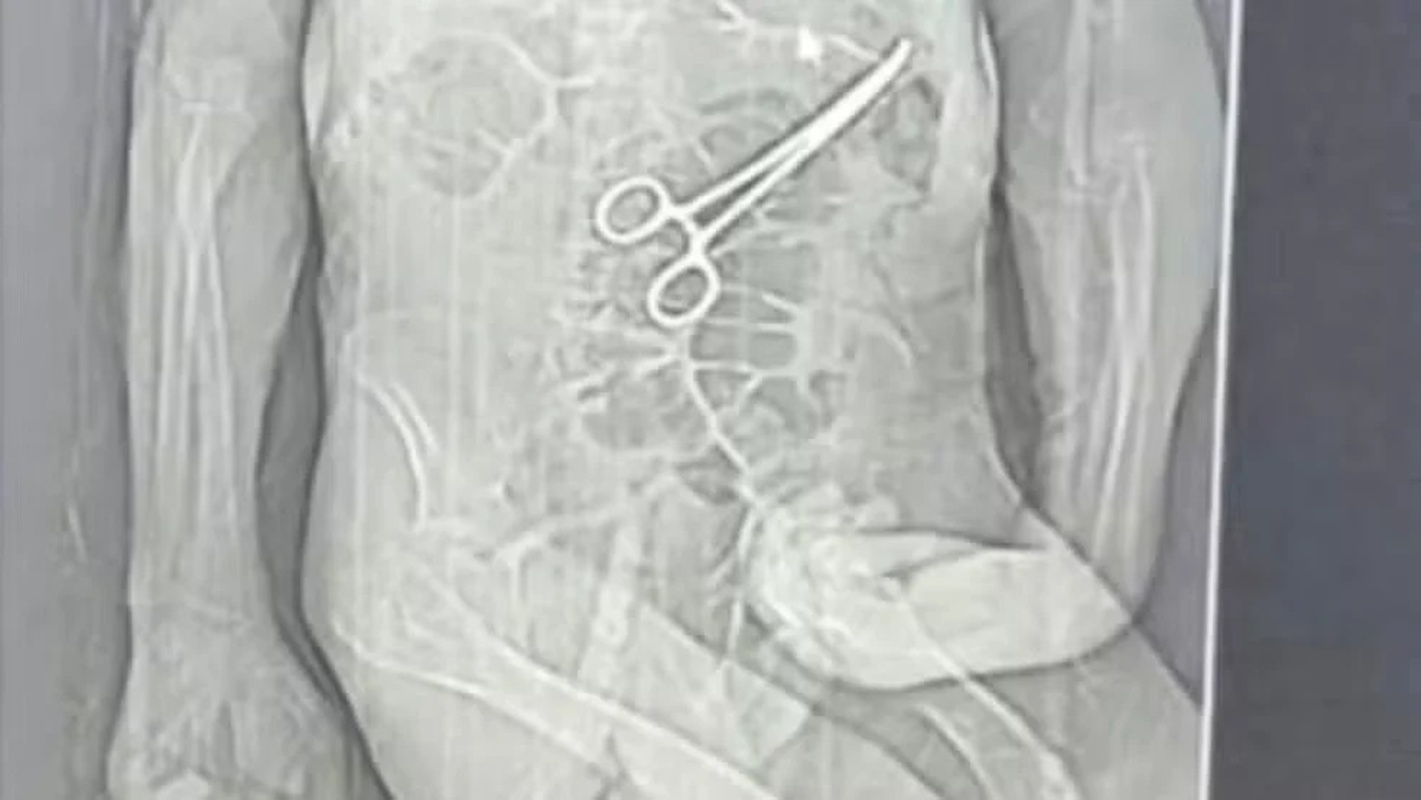

• Homem morre após pinça ser deixada no corpo em cirurgia

Homem morre após pinça ser deixada no corpo em cirurgia

Um homem, de 68 anos, morreu na véspera do Natal, após passar por duas cirurgias no Hospital Municipal de João Pinheiro, no noroeste de Minas Gerais. A família de Manoel Cardoso de Brito acusa a unidade de saúde de erro médico e afirma que uma pinça cirúrgica foi esquecida dentro do corpo do paciente após o primeiro procedimento.

A Secretaria Municipal de Saúde confirmou que houve a retirada de um corpo estranho durante a cirurgia e informou que abriu uma sindicância para apurar o caso.